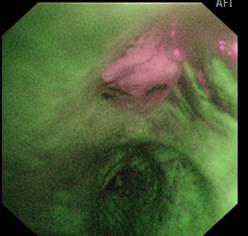

右主支气管: 荧光支气管镜(左图) 白光支气管镜 (右图)

术后病理示鳞状细胞癌,并准确判断手术切除范围。